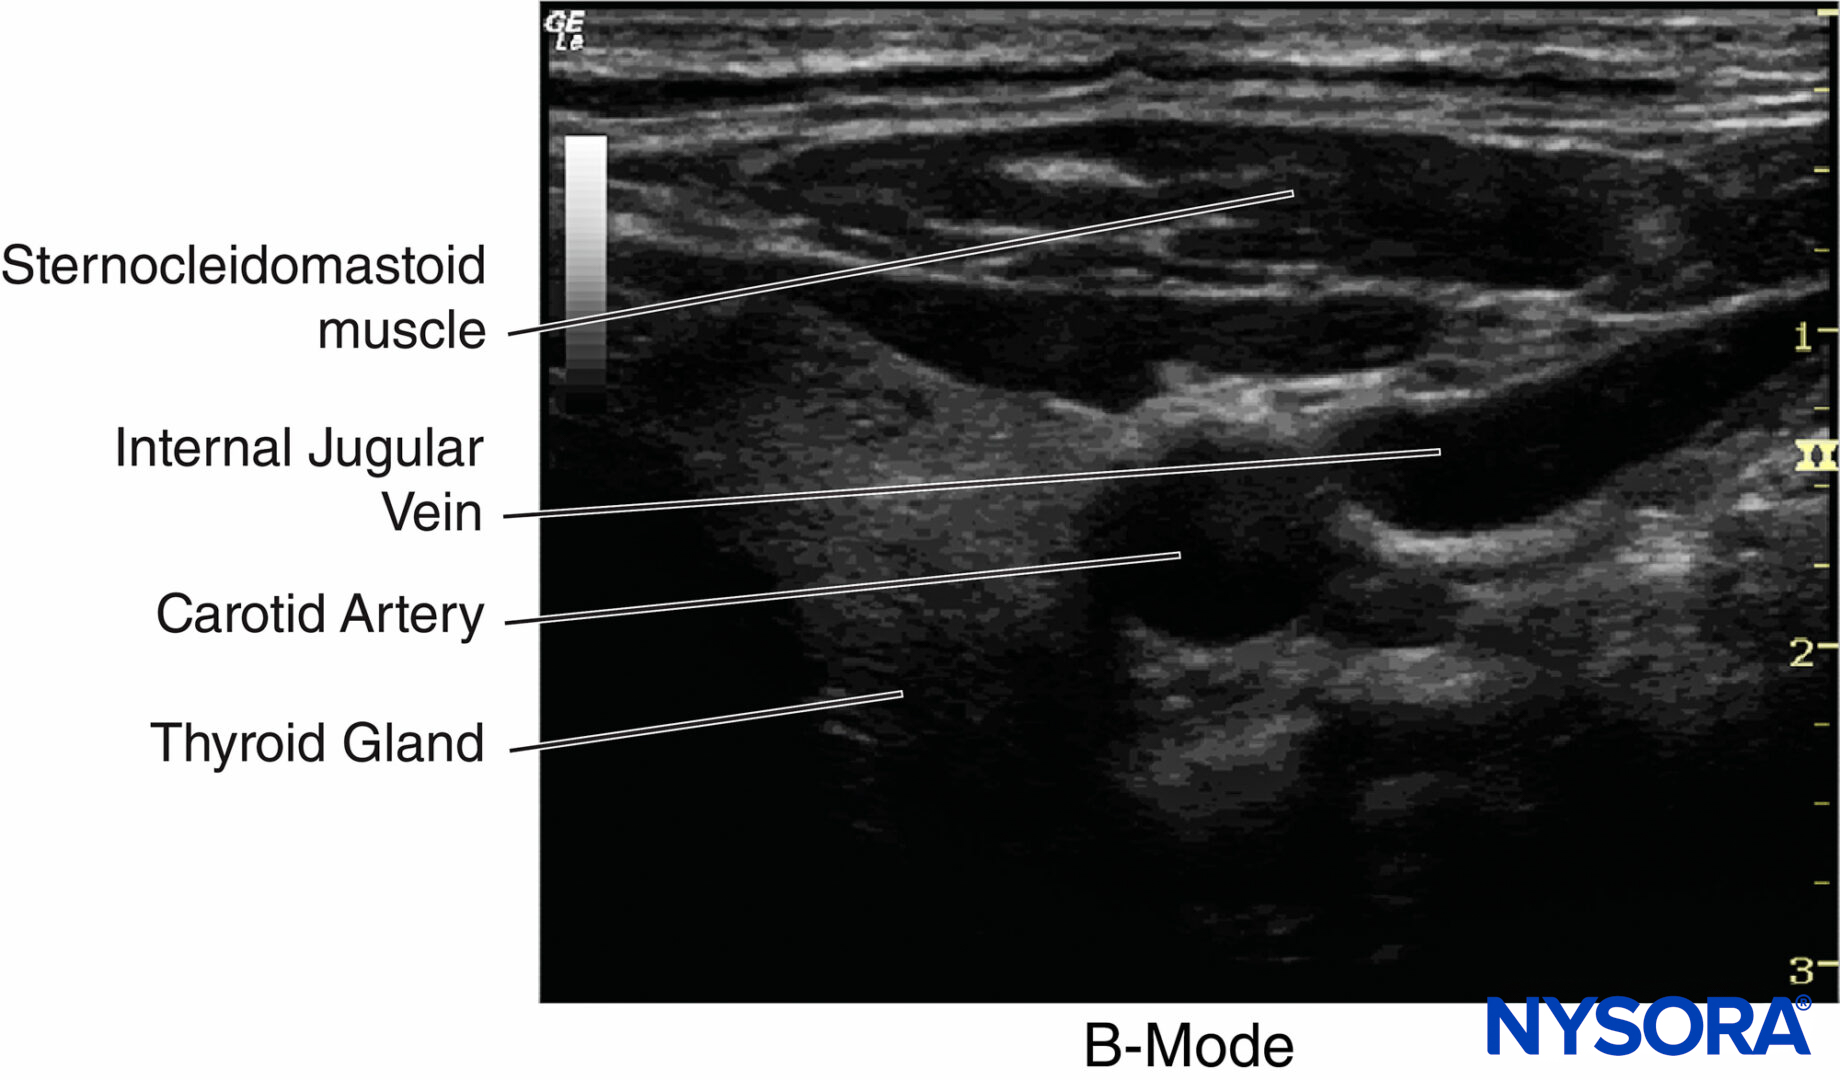

The B-mode is a two-dimensional (2D) image of the area that is simultaneously scanned by a linear array of 100–300 piezoelectric elements rather than a single one as in A-mode (Figure 9). The amplitude of the echo from a series of A-scans is converted into dots of different brightness in B-mode imaging. The horizontal and vertical directions represent real distances in tissue, whereas the intensity of the grayscale indicates echo strength (Figure 10). B-mode can provide an image of a cross section through the area of interest, and it is the primary mode currently used in regional anesthesia.

Figure 10. An example of B-mode imaging. The horizontal and vertical directions represent distances and tissues, whereas the intensity of the grayscale indicates echo strength. (Adapted with permission from Hadzic A: Hadzic’s Peripheral Nerve Blocks and Anatomy for Ultrasound-Guided Regional Anesthesia, 2nd ed. New York: McGraw-Hill, Inc; 2011.)